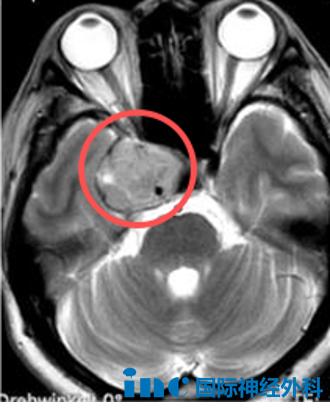

曾长期被视为"手术禁区"的海绵窦区,因解剖结构复杂且神经血管密集,至今仍是神经外科高风险区域。

手术难度主要源于病变位置深在且解剖关系复杂。该区域不仅包绕颈内动脉,同时密集走行动眼神经、滑车神经、三叉神经和外展神经等重要颅神经。术中轻微操作偏差可能导致神经功能障碍。因此,手术核心目标是在最大限度保护血管与神经功能基础上,实现病变最大程度切除。